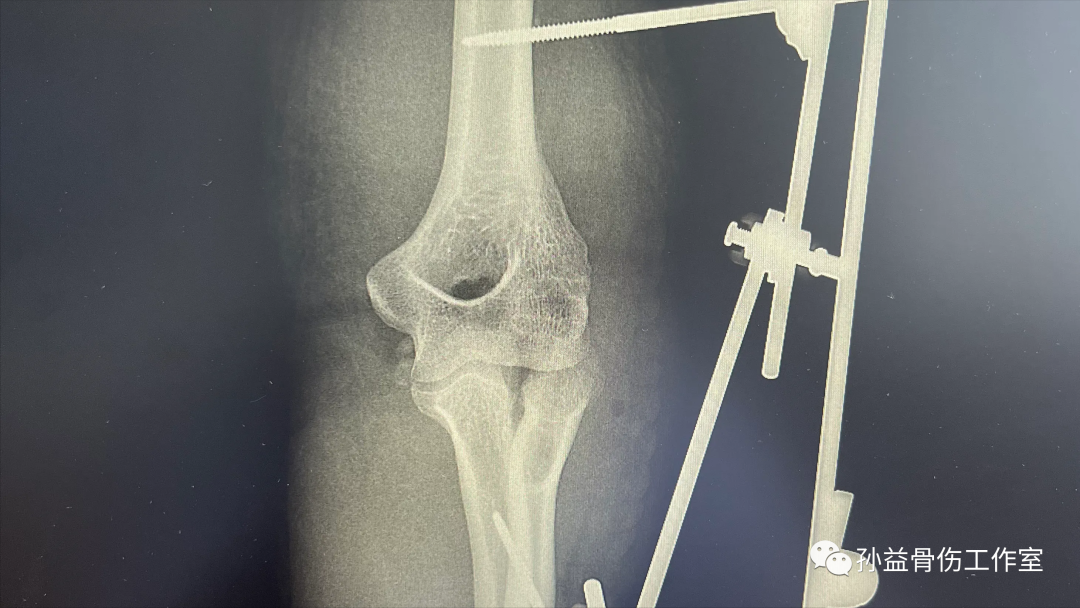

好在現代的外科手術技術不斷進步,住院后積極完善了相關的檢查,并根據檢查結果制定了手術方案,將近三個多小時的手術使得他畸形的肘關節恢復到理想的位置,手術的成功也讓他多了些欣慰,希望自己快點好起來甚至能夠早日工作上班。